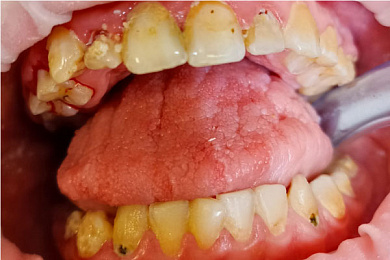

Процедура гигиенической чистки детям проводится по медицинским показаниям, в возрасте от 2,5 лет. Используются щадящие технологии очистки ClinPro и специальный, мягкий абразивный состав, обладающий приятным, сладковатым вкусом..

Показаниями считаются следующие симптомы::

- Повышенное количество зубного налета

- Отложения зубного камня

- Процессы воспаления дёсен

- Регулярная профилактика заболеваний полости рта